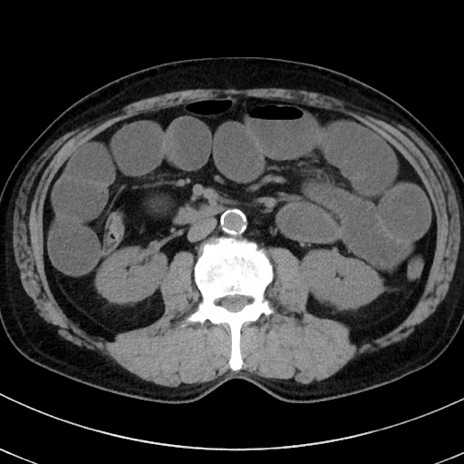

冠状断像

症例38(横断像)

【症例】70歳代 男性

【主訴】腹痛・嘔吐

【現病歴】昨晩より、嘔吐・腹痛あり。今朝になっても嘔吐あり。来院。

【既往歴】心臓バイパス手術、開腹胆摘、腸閉塞

【身体所見】BP 107/71mmHg、HR 116/min、腹部:平坦、軟、下腹部に軽度圧痛あり。反跳痛なし。

【データ】WBC 15100、CRP 0.32